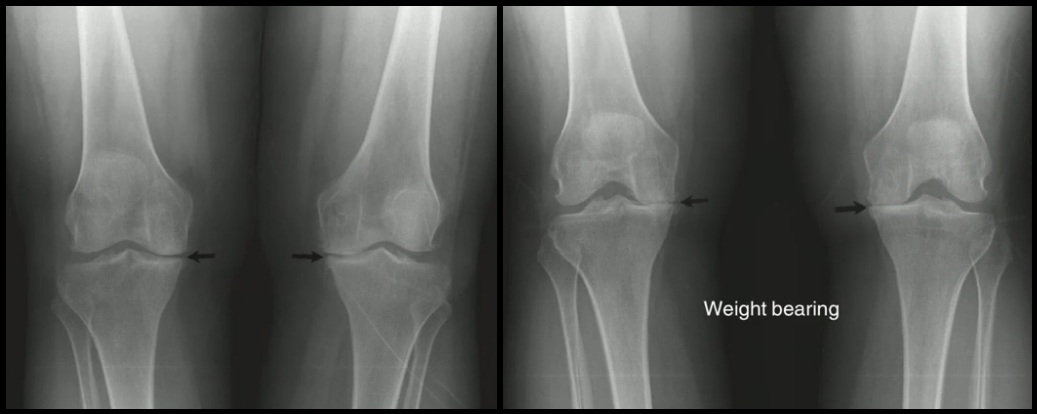

Incidências RX complementares (3)

• AP com Carga

• Rosemberg (PA com carga, Joelho fletido 45º, Raio incidindo na fossa poplítea com angulação Cranio-Caudal 10º)

• Panorâmico → Avaliar Varo/Valgo